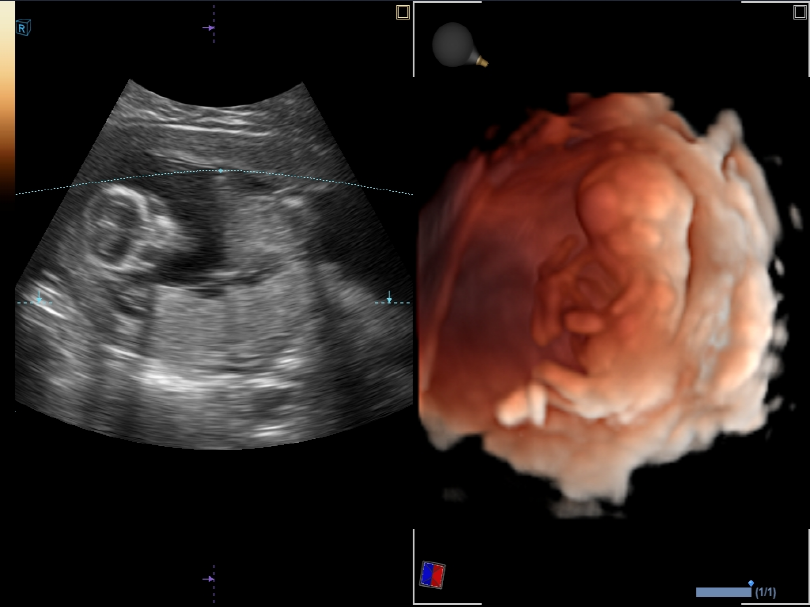

X CUBE 70 Elite

ECUBE 8 máy siêu âm thông minh cho công việc hàng ngày của bạn

Cung cấp cả sự tiện lợi khi sử dụng và quy trình chẩn đoán nhanh chóng và chính xác, E-CUBE 8 sẽ trở thành một đối tác tuyệt vời cho công việc của bạn. Bệnh nhân của bạn sẽ nhận được dịch vụ và chăm sóc riêng lẻ,

và năng suất của chăm sóc sức khỏe cũng sẽ được cải thiện. E-CUBE 8 là một sản phẩm thông minh, đáng tin cậy đảm bảo hiệu suất cao với chất lượng hình ảnh vượt trội và khả năng sử dụng đa mục đích. E-CUBE 8 là sự lựa chọn hợp lý nhất dành cho bạn.